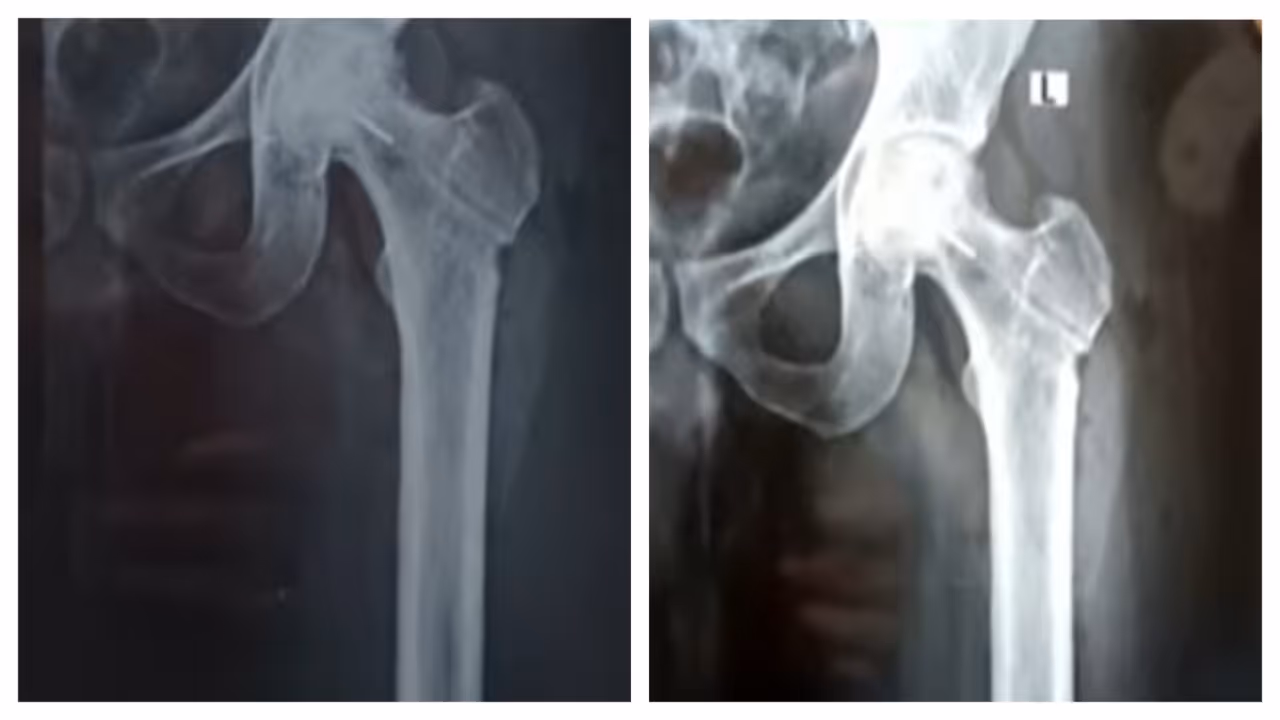

തിരുവനന്തപുരം: തിരുവനന്തപുരം ജൂബിലി മെമ്മോറിയൽ ആശുപത്രിക്കെതിരെ ഗുരുതര ചികിത്സാപിഴവ് പരാതി. ഇടുപ്പ് എല്ലിൽ ശസ്ത്രക്രിയ ചെയ്യുന്നതിനിടെയാണ് ചികിത്സ പിഴവുണ്ടായിരിക്കുന്നത്. രക്തയോട്ടം കൂട്ടാനുള്ള ശസ്ത്രക്രിയക്കിടെ ഡ്രിൽ ബിറ്റ് ഒടിഞ്ഞു കയറുകയായിരുന്നു. മലയിൻകീഴ് സ്വദേശി ജിജിൻ ജോസിൻെറ ഇടത് ഇടുപ്പ് എല്ലിലാണ് ഡ്രിൽ ബിറ്റ് ഒടിഞ്ഞു കയറിയത്. ജിജിൻെറ പരാതിയിൽ കൻോൺമെന്റ് പൊലീസ് കേസെടുത്തിട്ടുണ്ട്. ലോഹ കഷണം നീക്കം ചെയ്യാനാകില്ലെന്നും ലോഹ കഷണം ഇരിക്കുന്നതിനാൽ പ്രശ്നങ്ങളുണ്ടാകില്ലെന്നും രോഗിയെ അറിയിച്ചതാണെന്ന് ആശുപത്രി അധികൃതർ വ്യക്തമാക്കുന്നു.